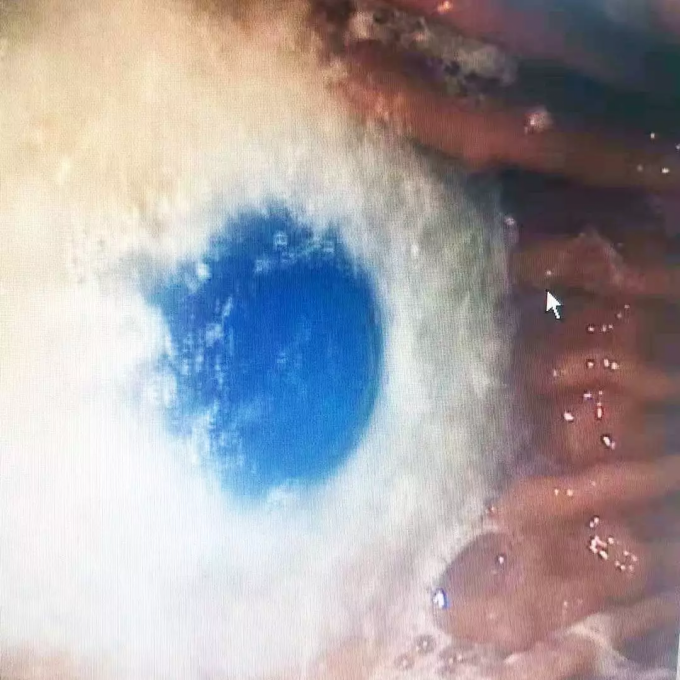

进镜后于胃底体交界处可见一蓝色圆形异物(泡大珠),此时泡大珠已膨胀至1.5cm×1.5cm,脆性增加,为防止在取出过程中泡大珠碎裂,不能完整取出可能会对患儿身体造成二次伤害,术中使用了一次性网兜套圈,完整将异物套住,顺利取出。术后,再次观察泡大珠完整,患儿无不适。